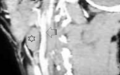

В диагностике боковой кисты шеи большое значение имеет КТ в режиме контрастирования, которая позволяет уточнить локализацию, топографические особенности ее расположения, размеры, плотность содержимого и состояние региональных лимфатических узлов.

На КТ шеи (слева) обозревается наличие инкапсулированной кисты, расположенная кпереди грудино-ключично-сосцевидной мышцы, на уровне подъязычной кости и щитовидного хряща. Форма кисты веретенообразная, размеры 3 см в переднезаднем и 2,5 см в поперечном измерение: вертикальный размер не менее 5 см. Внутри она имеет однородное кистозно-жидкостное содержимое (серозный мукоид) плотностью до 26 ед Н. Сонные артерии и внутренняя яремная вена расположены позади и медиальнее кисты - непосредственно прилегают к ее внутренней поверхности .

На КТ справа по переднебоковой поверхности шеи кпереди от сосудисто-нервного пучка, медиальнее от грудино-ключично-сосцевидной мышцы обозревается плотная тканевая структура которая проецируется на уровне подъязычной кости и щитовидного хряща. Размеры 4х2,5 см. Сонные артерии и внутренняя яремная вена оттеснены медиально.

Заключение: плотная тканевая структура по переднебоковой поверхности шеи (с права) расположенной кпереди от сосудисто-нервного пучка шеи (по структуре очевидно можно предполагать наличие смешенной доброкачественной опухоли).